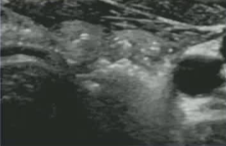

PLA平尖技术。A、使用21 g千叶针将300 μm平面切割光纤穿过鞘,根据病变大小,将裸露的光纤直接接触甲状腺组织,暴露长度为5 ~ 7 mm。B,当输出功率为2 ~ 4瓦,能量为1600 ~ 1800焦耳时,单根保持静止的光纤仅破坏少量组织(长16 ~ 18 mm,宽8 ~ 10 mm,厚8 ~ 10 mm,即约1ml体积)。

电极在超声引导下进入目标结节,并不断重新定位涂抹器(“移动消融激素”或“多重重叠消融”技术)导致椭球状坏死区域。